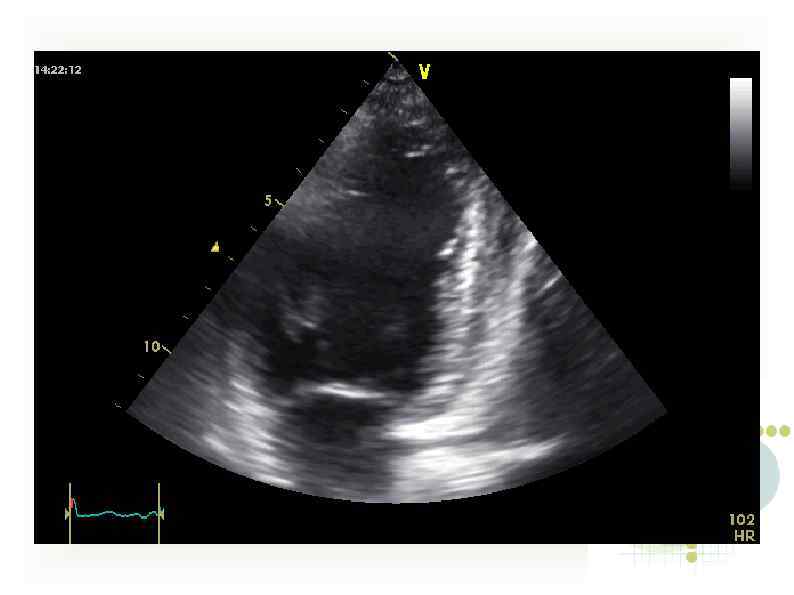

Эхо-КГ 16/09/11 (ЧСС - 140 -150/мин!) Диффузный гипокинез стенок левого желудочка, ФВ 55%. Митральная Эхо-КГ 16/09/11 (ЧСС - 140 -150/мин!) Диффузный гипокинез стенок левого желудочка, ФВ 55%. Митральная регургитация II степени, трикуспидальная регургитация II степени. Признаков легочной гипертензии нет.